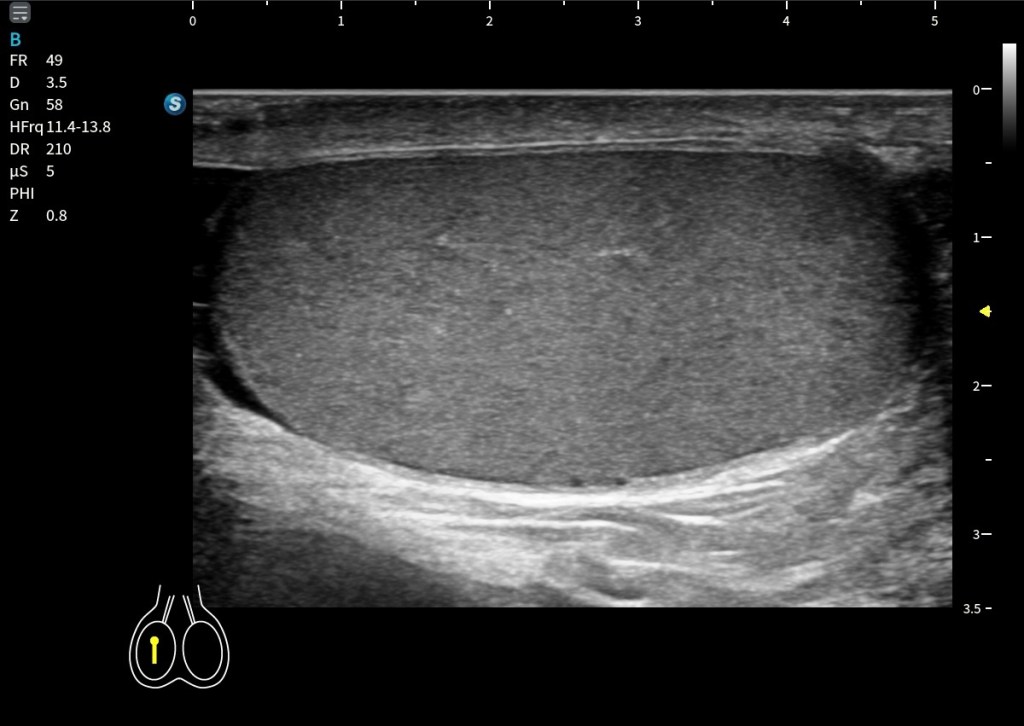

El Platisma es un músculo superficial, plano y muy fino, situado justo por debajo de la piel y del tejido celular subcutáneo, es el músculo más superficial del cuello.

Por encima de él solo encontramos piel y grasa, tejido celular subcutáneo en más o menos medida. Por debajo, ya entramos en estructuras más profundas del cuello anterior.

Por eso, el Platisma tiene una importancia clave: Marca el límite entre lo superficial y lo profundo en el cuello.

Una vez optimizada la técnica, el platisma se reconoce como una estructura muy fina, hipoecogénica, de aspecto plano y continuo, sin un patrón fibrilar tan evidente como el de otros músculos, repito muy variable en su presentación. Se localiza entre la grasa subcutánea, que es más ecogénica, y los planos musculares profundos, que presentan una arquitectura más definida. Podemos identificarlo como entre dos laminas hiperecogénicas. Como un bocadillo. El ECM siempre nos va a ayudar, un buen libro de anatomía del cuello al lado, tambien.